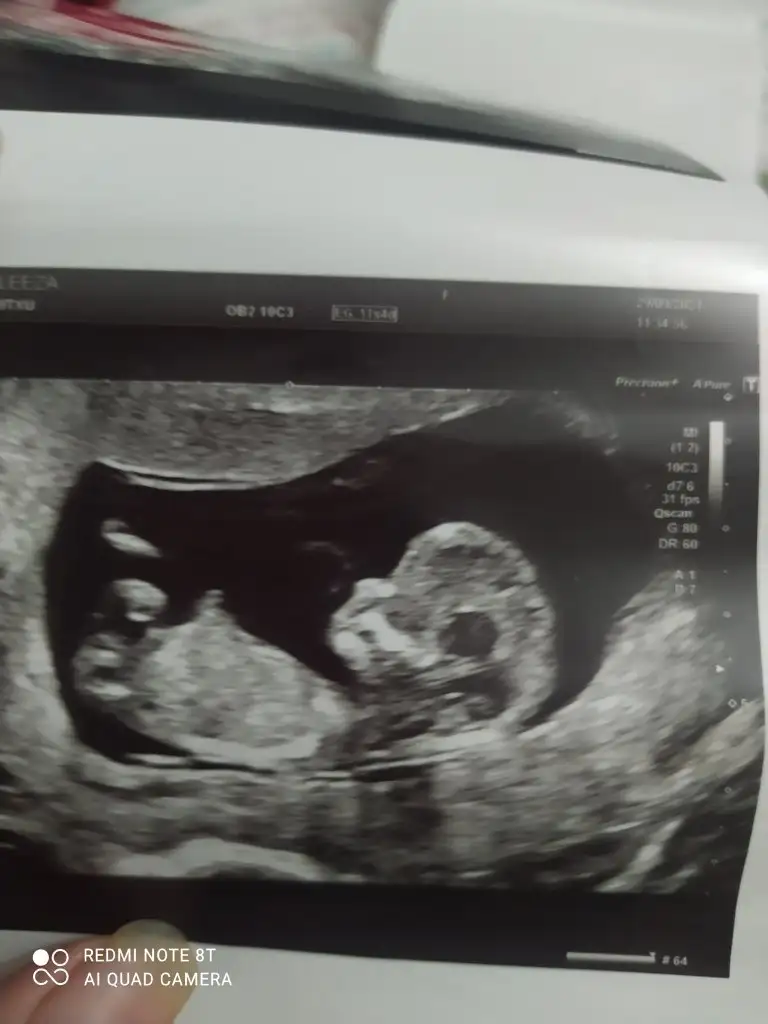

Doktor erkek gibi duruyor dedi ama bakalim net değilEmin olamadım kız gibi sanki

Emin olamadım ama sanki kız gibi

Tahmininiz doğru çıktı haber vermek istedimErkek gibi sanki

Kız gibi sankiIkra meyra